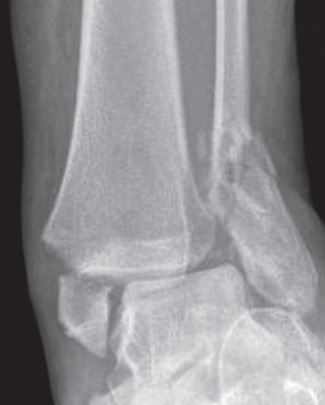

Mens Annette snakket om viktigheten av å fiksere med «belte og bukseseler» i gammelt, skjørt ben, fortalte Marius at svært mange ankelbrudd - også hos eldre - kan behandles konservativt så lenge ankelgaffelen er stabil og kongruent ved belastning. Mindre fokus på antall millimeter dislokasjon av fibula og mer fokus på at talus står midtstilt under tibia ved belastning, var Marius’ mantra. Og dropp gipsen. Hos de som er operert kan man bruke en walker i noen uker for å beskytte såret, men gips er neppe nyttig.

Begge var enig i at om man må operere eldre med ankelbrudd må man gå for mye metall og belastningsstabil osteosyntese. Særlig hos de eldre som har redusert følelse i foten – delbelastning eller belastning til smertegrense er meningsløst for en diabetiker som ikke kjenner noe nedenfor kneet. Eller hos de som har gått på bruddet en uke eller to før de kommer til sykehuset.